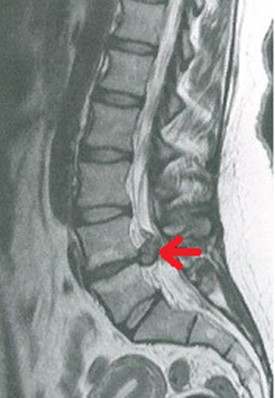

Na obrazie TK kręgosłupa strzałką wskazano wyrostek

A. poprzeczny.

B. kolczysty.

C. żebrowy.

D. stawowy.